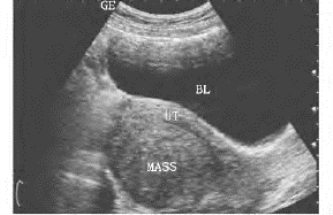

1.37.5五、非先天性子宫疾病

-